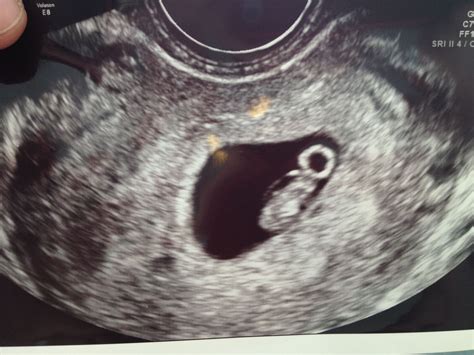

• Gestational Sac: The presence of a gestational sac confirms the pregnancy. It appears as a small, fluid-filled structure within the uterus.

• Yolk Sac: By week 6, a yolk sac may be visible. This structure provides early nutrition to the embryo and is a positive sign of a healthy pregnancy.

• Fetal Pole: The fetal pole is the earliest visible structure of the embryo. It appears as a small, curved line within the gestational sac.

• Fetal Heartbeat: A fetal heartbeat may be detectable by week 6, although it is more commonly seen by week 7. The heartbeat appears as a flickering motion on the ultrasound screen.